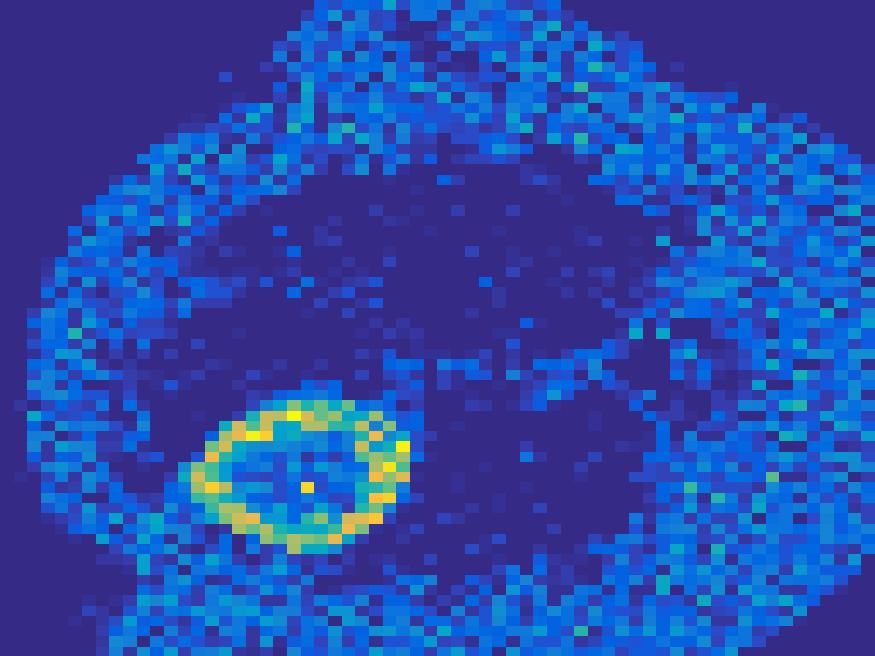

Figure 8 and 9 show the results of the ellipse and rat phantom with Poisson noise. Since the number of projections is very limited and the corruption by Poisson noise, the reconstruction by both FBP and EM (with updating basis) are not satisfactory, while the proposed method is capable to reconstruct the main structure of the images faithfully.

We also perform Monte carlo simulation on the more complex images: the rat’s abdomen phantom. By setting , the sinogram image is shown in Figure 17.

The images reconstructed can be found in Figure 18 for . Figure 19 illustrates the comparison of the true TACs and those reconstructed by the proposed method. We can see that the proposed method is robust to reconstruct most of the structures present in the images.